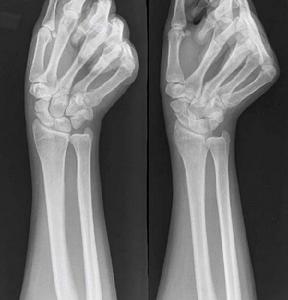

3、X線檢查

除正、側位X線攝片外,尚應根據傷情拍攝特殊體位相,如開口位(上頸椎損傷)、動力性側位(頸椎)、軸位(舟狀骨、跟骨等)和切線位(髕骨)等。複雜的骨盆骨折或疑有椎管內骨折者,尚應酌情行體層片或CT檢查。

腕舟狀骨骨折X線平片的診斷意義 常規腕關節正側位片、舟狀骨位片可以清晰顯示關節間隙,腕骨夾角以及其他腕骨結構,對診斷腕舟狀骨結節骨折,尺橈骨遠端骨折及其他腕骨骨折脫位很有意義。但常因投照技術、體位、角度等因素使舟狀骨骨折漏診。同時還有一部分穩定型骨折,因骨折端嵌插,其平片常呈高密度影,未見低密度骨折線而漏診。本組3例複習初次X線平片為高密度影,當時未行固定,致骨折線明顯後才確診。有學者認為,傷後2~3周,隨著骨折斷端骨質壞死及血腫的吸收,骨折處間距加大,可以提高X線平片的診斷率。但亦有學者研究則認為傷後2~3周與初次的X線表現常無變化。本組2~3周X線確診率為37.5%,4~6周為100%。